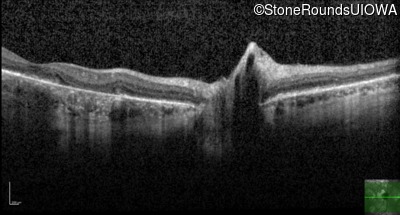

Optical Coherence Tomography - Left - 20/50 -2 sc

Exemplar / OCT Stack